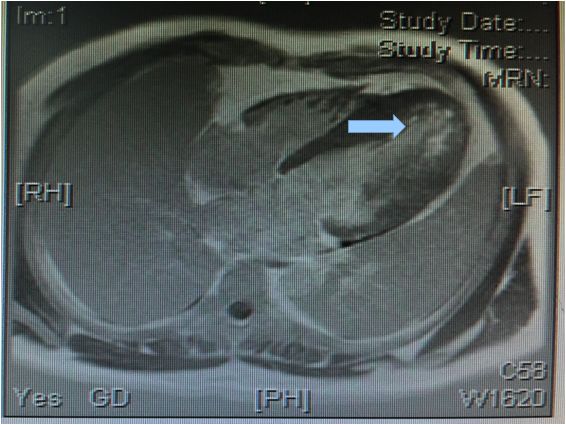

左房饱满,左室不大,前间隔及其余左室各中远段及心尖部增厚(最厚16-21mm)

舒张期心尖呈“黑桃尖”样改变,收缩末左室腔中部几近闭塞,心尖室腔呈裂隙样

左室基底段厚度大致正常或高限,收缩功能大致正常,左室流出道未见梗阻征象

心肌首过灌注左室心尖部可见心内膜下灌注减低

延迟扫描室间隔远段及左室心尖部可见心内膜下强化信号